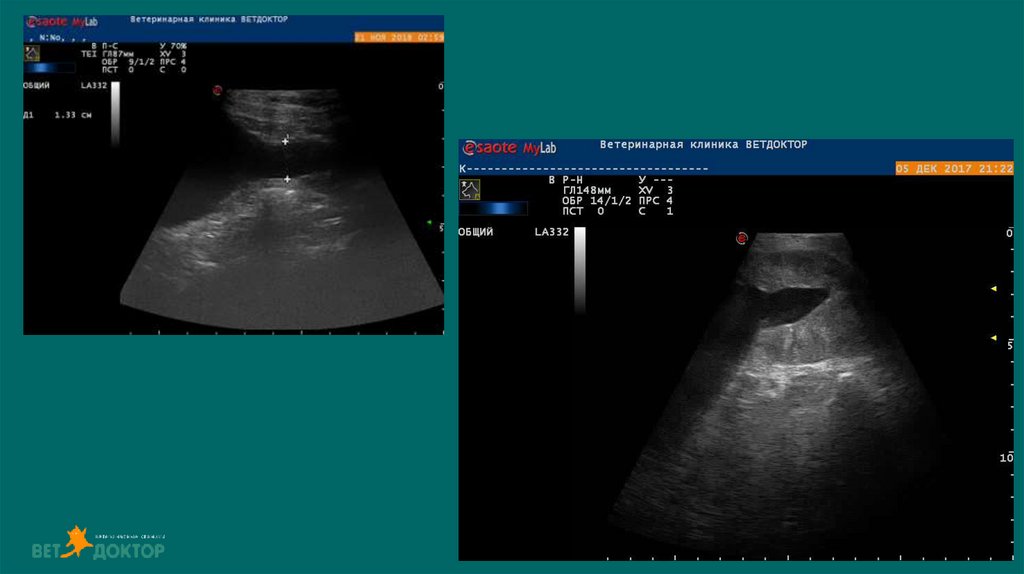

19. Ультразвуковое исследование

Можем обнаружить рентгенпрозрачные уролиты ,оценивать архитектуру

почки, паранефральные ткани, ретроперитониальные ткани, кисты

,инфартуи ы почек, изменение эхогенности, неоплазию, расширение

почечных лоханок и мочеточников, измерить толщину стенки мочевого

пузыря, визуализировать свободную жидкость в брюшной полости

УЗИ мониторинг изменений картины мочевой системы

• размер уретры

• размер лоханки и мочеточников

• количество свободной жидкости

38. УЗИ

Дилатация лоханки более 13 мм - обструкция

При диаметре лоханки более 8мм-высокая

вероятность обструкции